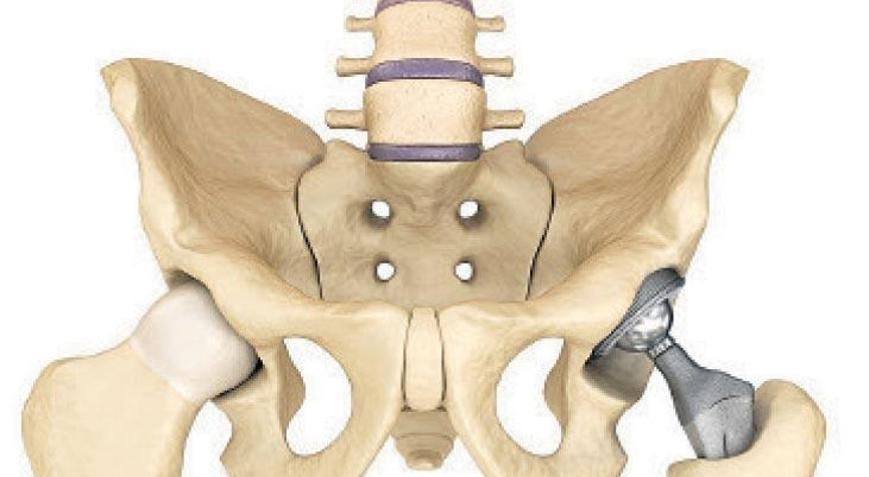

Modern teknoloji ve tıptaki gelişmeler sayesinde ortopedik rahatsızlıkların tedavisinde büyük ilerleme sağlandığını belirten Ekol Hastanesi Ortopedi ve Travmatoloji Uzmanı Opr. Dr. Mehmet Akdemir, eklem rahatsızlıklarında kullanılan protez (diz, kalça, omuz, ayak bilek vb.) implantları ve ameliyat tekniklerinde önemli gelişmeler olduğunu anlattı.

Eklem hasarının çok fazla olmadığı durumlarda, ağrı kesiciler, fizik tedavi uygulamaları, eklem içi ilaç enjeksiyonları, PRP ve kök hücre uygulamalarının uygulanabileceğini belirten Akdemir, ”Eğer eklem onarılamayacak derecede hasar görmüş ise tedavi seçenekleri içinde artrodez (eklem dondurması) veya artroplasti (eklem protezi) öne çıkıyor. Artrodez eklem hareketinin ortadan kaldırılmasıdır. Küçük eklemlerde (örneğin parmak) hala en iyi tedavi seçeneği olmakla birlikte büyük eklemlerde (kalça-diz) ciddi fonksiyon kaybına neden olduğu için hastalar ve hekimler tarafından artrodez tercih edilmez” dedi.